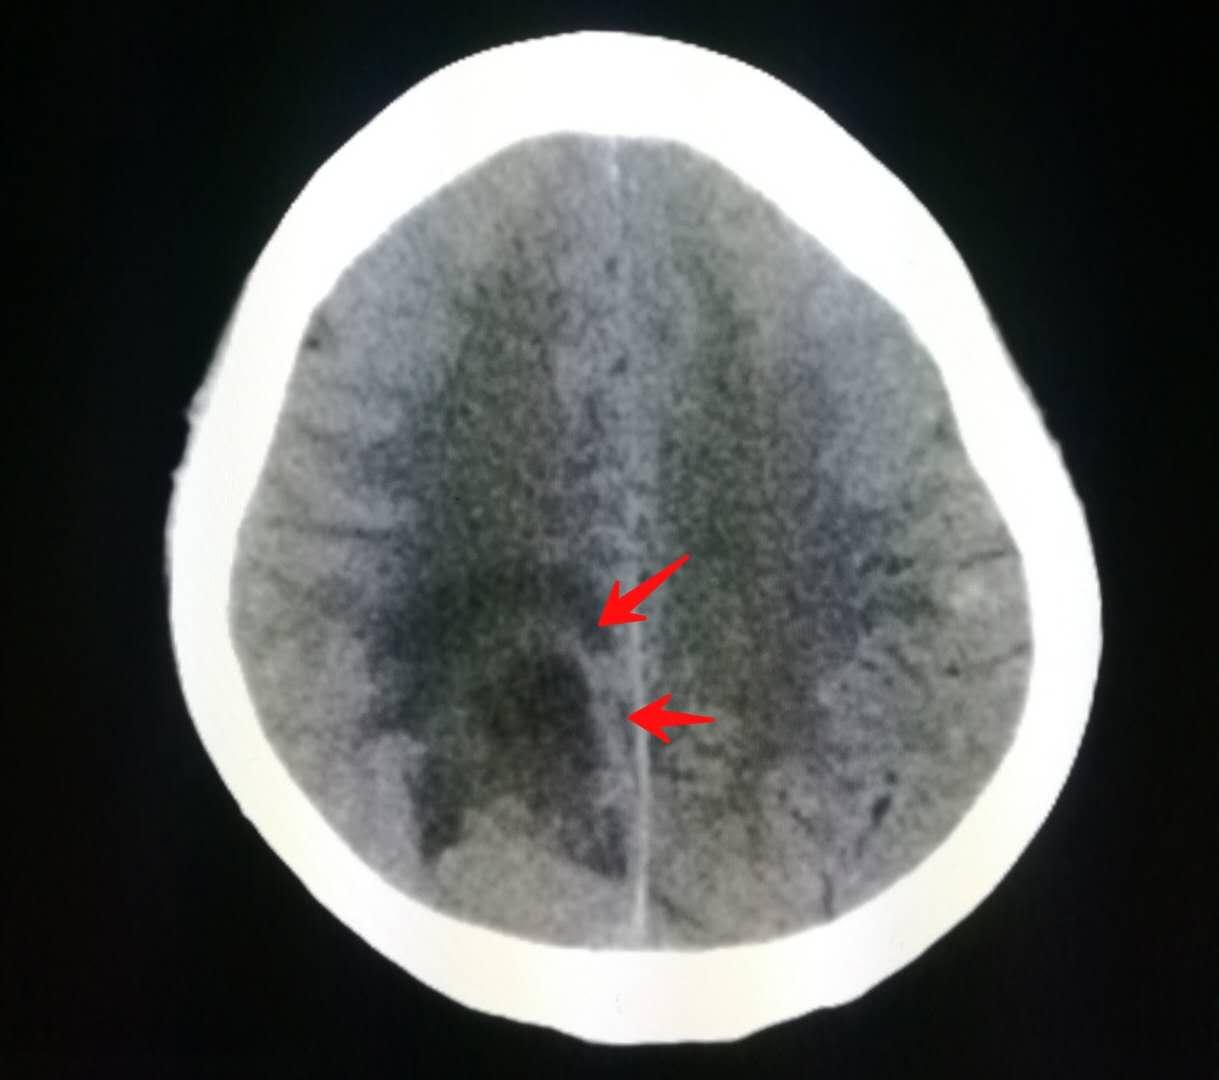

上周值夜班,一位60多岁的退休老人在家弹钢琴时,突然发现小指和无名指无力,按不动琴键。

急诊科医生说,先做颅脑CT吧,排除脑梗死。

结果却是脑转移瘤,是肺癌发生了脑转移,但老人还没有出现肺部症状。

下图就是上周夜班遇到的那位老人,老爷子是一位退休干部,喜欢音乐,在家里弹钢琴的时候突然感觉左侧小指和无名指使不上力,按不动琴键了。

来医院做了脑部核磁共振,发现了脑转移瘤:

紧接着做了胸部CT,证实为右侧肺癌,老人没有任何肺部症状: